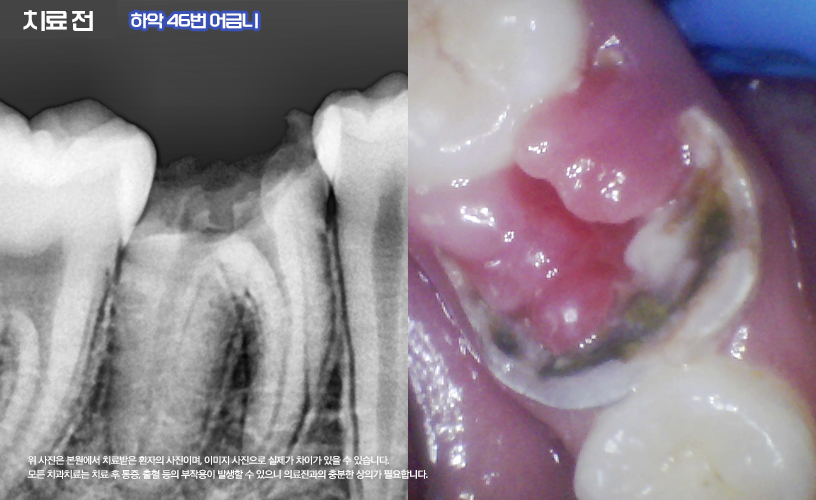

나머지 상, 하악 16,26,36,46번 치아는

신경치료를 통해 치료가 진행됩니다.

먼저 충치로 인해 파절의 정도가 심한 상태이기

때문에 신경치료와 함께 포스트+레진 코어를 통해

얼마 남지 않은 치아의 기둥을 세워

튼튼하게 잡아주었습니다.

또한 환자분의 경우 우식이 깊은 상태였기 때문에

치관의 모양이 상실된 상태에서 우식이

치은연하(잇몸 아래)으로 진행되어

신경치료 전 치은 절제술까지 함께 진행되어

치관의 길이를 확보하는 시술이 추가되었습니다.

본 원의 치은 절제술은 절개를 하지 않고

전기 소작기를 이용하여 출혈이

거의 없도록 진료가 이루어집니다.